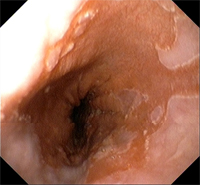

¿Qué es el esófago de Barrett?

El esófago de Barrett es una alteración de la mucosa de esófago que, como consecuencia del reflujo gastroesofágico persistente, se inflama tanto que incluso llega a cambiar de características histológicas. Este cambio de tejido es la única característica que nos permitirá hacer el diagnóstico, es decir, el diagnóstico de esófago de Barrett no se puede establecer por el aspecto de la mucosa en la endoscopia ni por los síntomas del paciente ni por la demostración de un exceso de ácido refluido. Lo único que nos da el diagnóstico es demostrar que en el esófago se encuentra tejido de tipo intestinal (lo que se conoce como metaplasia intestinal) y si no hay tejido de estas características no se puede hacer el diagnóstico de esófago de Barrett.

La alteración de la mucosa que se observa en estos pacientes necesita ser controlada periódicamente porque en muy pocos casos la inflamación puede provocar degeneración del tejido y es necesario detectarlo de forma precoz para poder tratarlo.